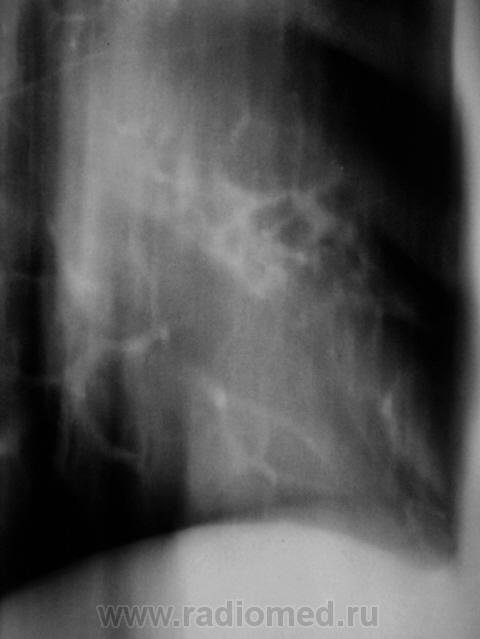

Еще контроль через 1 месяц.